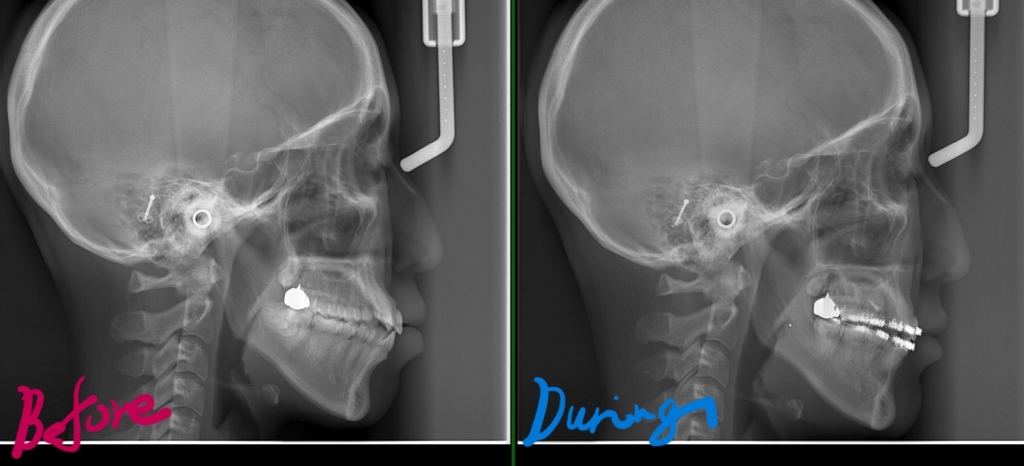

【途中経過】 当初に抜歯をして出来たスペース分は、しっかりと引っ込めることが出来ました。

現状としては、ここまで口元が引っ込みました。

最初と比べてみると、

それでは、その間の変化をレントゲン写真で見てみましょう。

右側が智歯を抜歯してアンカースクリューを併用しながら歯列全体を引っ込めた後の状態、

歯列の途中の奥歯を抜歯するほどには変化させられませんが、智歯という普通は抜歯だけで済ませる歯を利用することで、このように「もう一声!」口元の変化を起こすことも可能です。